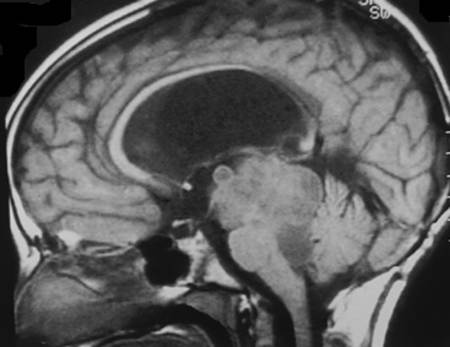

Investigadores de la Johns Hopkins dicen haber descubierto uno de los mecanismos celulares más importantes que impulsan el crecimiento y la progresión de los meningiomas, la forma más común de tumor de cerebro y la médula espinal. Un informe sobre el descubrimiento, publicado en la revista Molecular Cancer Research, podría abrir el camino al descubrimiento de mejores medicamentos para atacar estos tumores paralizantes, dicen los científicos.